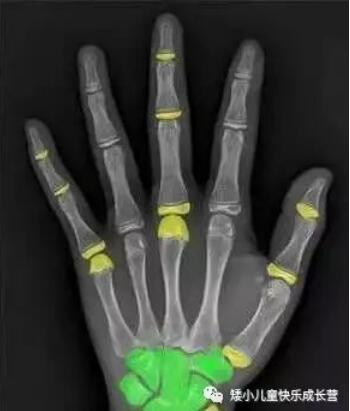

骨龄即骨骼年龄,骨龄是骨骼年龄的简称,它是以小儿骨骼实际发育程度同标准发育程度进行比较,所求得的一个发育年龄。骨龄在很大程度上代表了儿童真正发育水平,因此用骨龄来判定人体成熟度比实际年龄更为确切。及早了解儿童的生长发育潜力及性成熟的趋势,可以预测儿童的成年身高;骨龄的测定还对一些儿科内分泌疾病的诊断有很大帮助。

定期的测定骨龄是为了检测出孩子骨头的“真实年龄”,并且可以判断出孩子生长发育的情况,是发育过快,还是发育迟缓,从而做出综合判断。进行合理治疗。